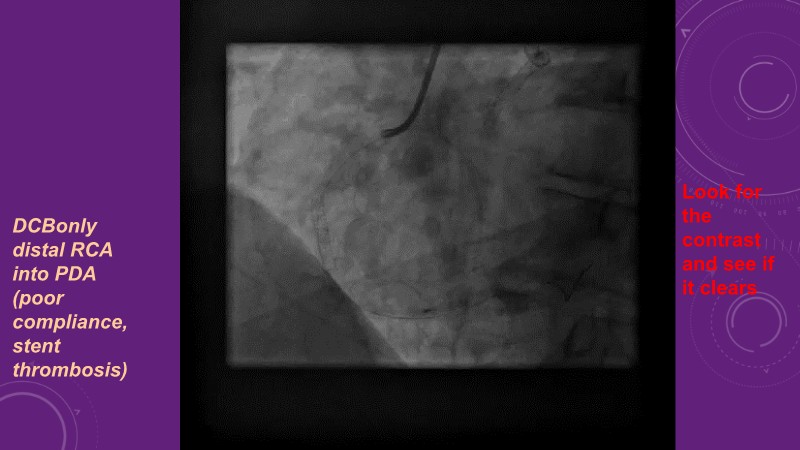

Leave nothing behind - Advancing DCB strategies in complex interventions

Explore cutting-edge strategies for optimizing drug-coated balloon (DCB) procedures in this session. Uncover practical tips to improve outcomes, review key indications, and examine international consensus on DCB use. Case presentations and expert discussions offer insights to refine your approach.